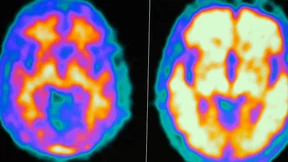

Erstmals steht Patienten mit Alzheimer ein Medikament zur Verfügung, das den Krankheitsprozess beeinflusst – bisher ist es allerdings nur in den Vereinigten Staaten zugelassen. Wissenschaftler prüfen zurzeit weitere Substanzen in Studien, und auch hinsichtlich der Diagnostik schreitet die Forschung mit großen Schritten voran.